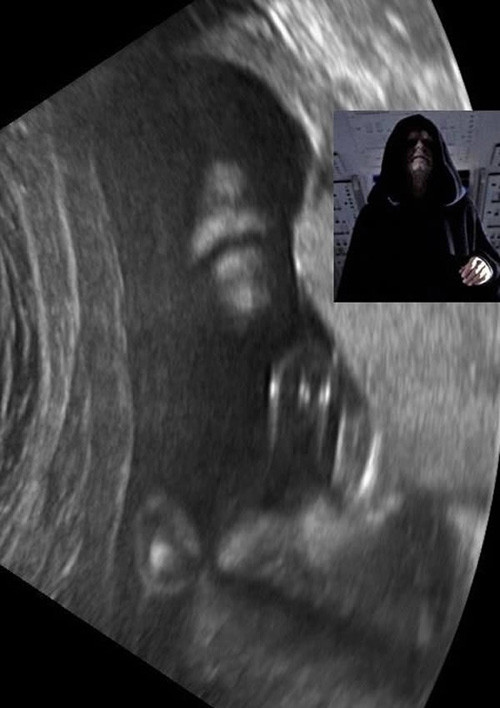

Cô Heather Large (39 tuổi) và chồng là Toby (33 tuổi), đến từ Pingree Grove, Illinois, Mỹ đã rất bất ngờ khi xem bức ảnh siêu âm thai nhi con của họ bởi hình ảnh siêu âm này giống hệt với nhân vật Hoàng đế Palpatine nổi tiếng trong bộ phim "Star Wars" (Chiến tranh giữa các vì sao).Hơn 4 tháng sau đó, bé trai chào đời mạnh khỏe trong sự vui mừng của vợ chồng nhà Large. Khuôn mặt cậu bé khi chào đời xinh như thiên thần và không có nét gì giống "Chúa tể hắc ám". Cậu bé được đặt tên là Bowie, hiện nay cậu bé đã được hơn 3 tuổi.